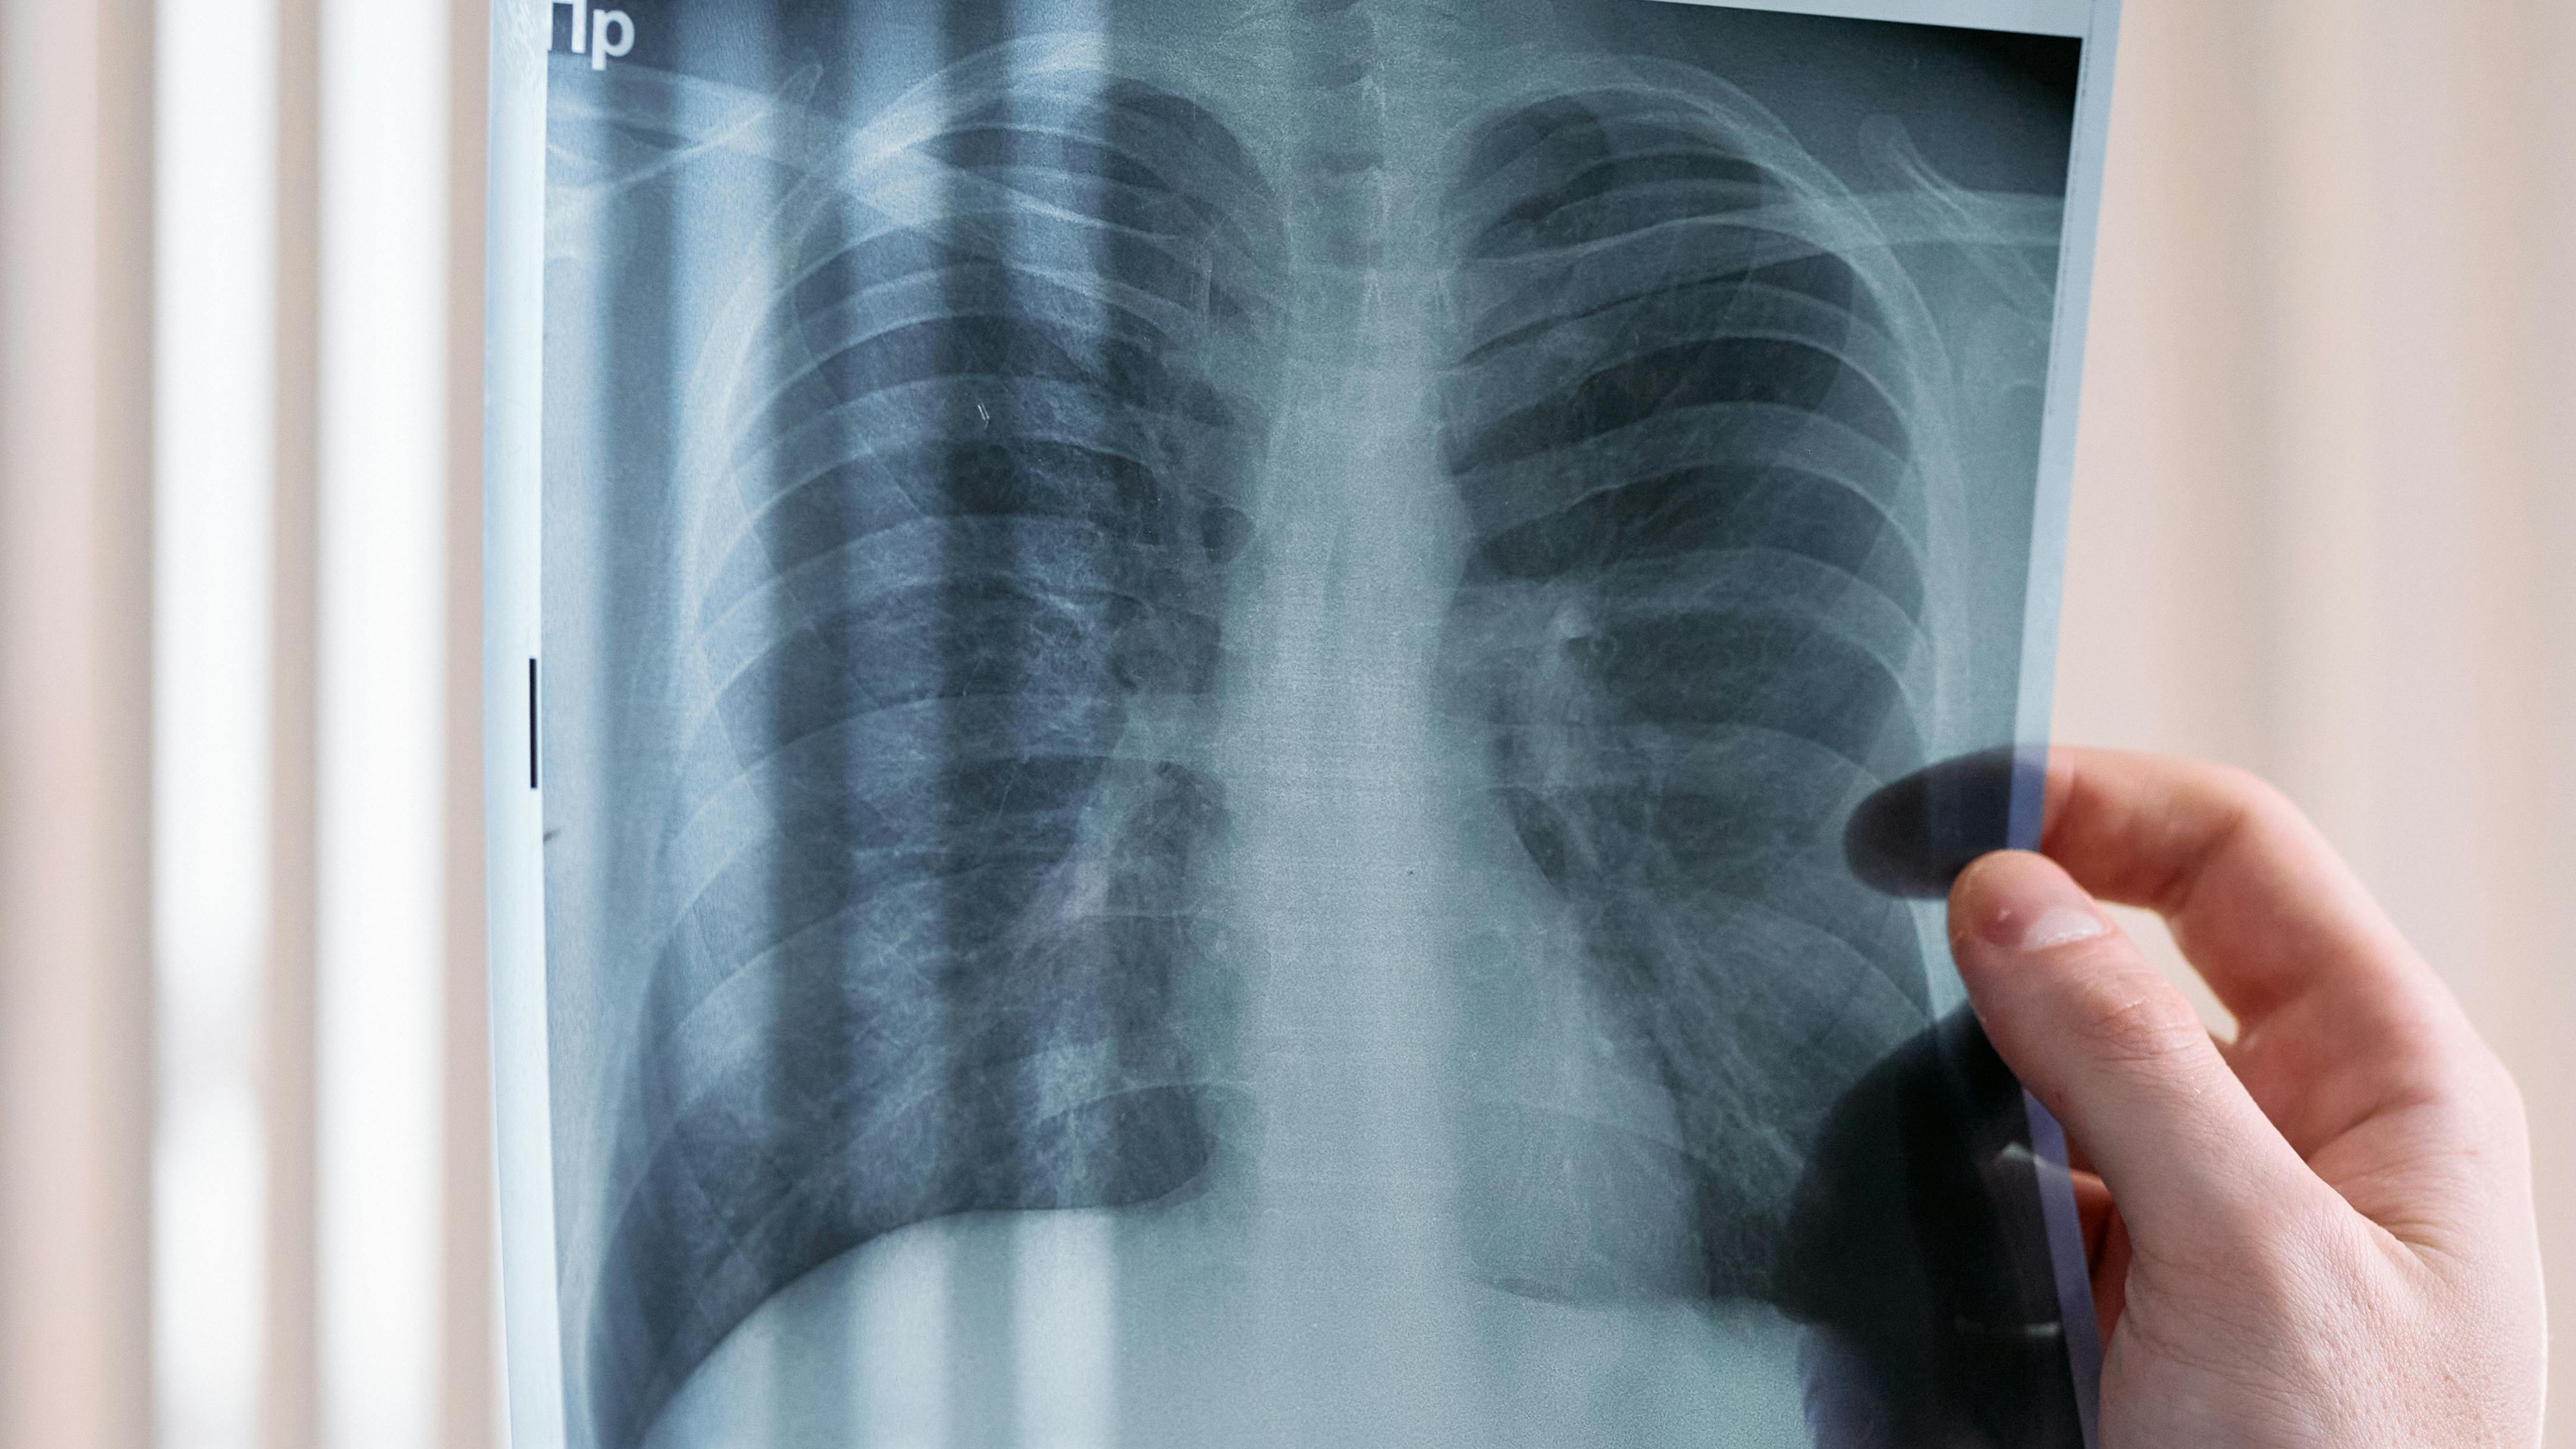

A CoruñaEl uso de la inteligencia artificial (IA) está revolucionando la Sanidad. Así como hace casi 130 años los rayos X se pusieron al servicio de la medicina y fue un hito que mejoró estratosféricamente los diagnósticos de muchas dolencias, la inteligencia artificial está siendo, en la actualidad, el complemento perfecto a esa tecnología del siglo XX.

En A Coruña, sin ir más lejos, en el Hospital Universitario de A Coruña (Chuac), donde cada año se realizan del orden de 500.000 estudios de radiodiagnóstico, la IA está resultando de vital importancia para evaluar esa ingente cantidad de imágenes y hacerlo en tiempo récord: menos de medio minuto por placa.

También en los 13 puntos de atención continuada (PAC) del área comarcal de A Coruña se valen desde hace tiempo del apoyo que proporciona la Inteligencia Artificial, en este caso, para ayudar a los médicos de familia a interpretar las radiografías sin necesidad de recurrir a los informes de los radiólogos.

Y a la vista los resultados: desde que se implantó el programa de algoritmos, hace aproximadamente un año del algoritmo han salido 23.000 estudios musculoesqueléticos, y las interpretaciones de 9.600 radiografías de tórax, unas cifras impensables años atrás sin esta herramienta “de indudables beneficios”, según Castro.